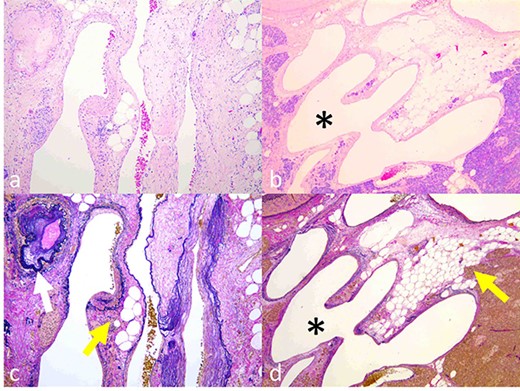

Based on these imaging findings, the patient was diagnosed with AVM in the pancreatic head and subsequently underwent subtotal stomach-preserving pancreaticoduodenectomy. Intraoperative ultrasonography revealed tortuous vessels in the head of the pancreas. Severe inflammation around the pancreatic head and adhesion between the pancreas and portal vein increased the complexity of the surgical procedure and hindered inflow control of the pancreas. To control bleeding, we first ligated and divided the arterial inflow into the pancreatic head. The operative time was 712 min, and the estimated blood loss was 1260 ml. Grossly, the specimens had dilated and tortuous blood vessels in the pancreatic head, development of elastic fibers with thickened arterial walls and dilated veins, and pancreatic parenchyma steatosis (Fig. 4). The transition from arteries to veins was not detected macroscopically. Microscopic examination similarly revealed the presence of dilated vessels in the pancreatic head, the majority of which were veins containing few smooth muscles and thick and ruptured elastic fibers (Fig. 5). Based on these histopathological findings, the postoperative diagnosis was AVM of the pancreatic head and pancreatitis.

Histopathological findings. (a, b) Dilated and tortuous veins and arteries. The transition from an artery to a vein was detected (b, asterisk). (c, d) Development of elastic fibers with thickening wall of arteries (c, colorless arrow) and dilated veins with steatosis of the pancreas parenchyma (c and d, colored arrow). (a, b) Hematoxylin–eosin staining; (c, d) Elastica van Gieson staining).